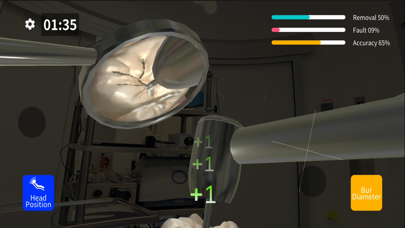

Dental MirrorMaster

Скриншоты